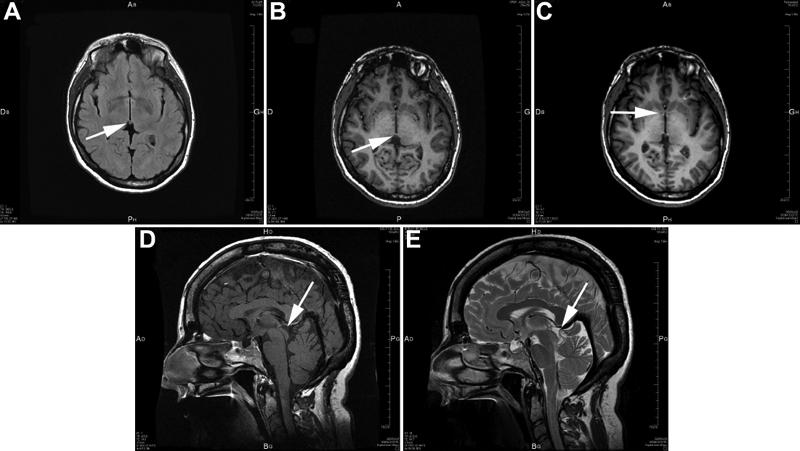

Three novel heterozygous mutations affecting three unrelated families were identified: the g.572T>C nucleotide change, located in exon 5, and corresponding to the Leucine 46 Proline amino-acid mutation (L46P); the g.655A>G nucleotide change, located in exon 6, and corresponding to the Serine 74 Glycine amino-acid mutation (S74G); and the nucleotide deletion 579delG del, located in exon 6, which induces a frameshift mutation leading to a stop codon (V48fsX53). The L46P mutation was identified in affected patients presenting bilateral microphthalmia, cataracts, and nystagmus. The S74G mutation was found in a large family that had congenital ocular abnormalities, diverse neurological manifestations, and variable cognitive impairments. The 579delG deletion (V48fsX53) caused in the affected members of the same family bilateral aniridia associated with congenital cataract, foveal hypolasia, and nystagmus. We also detected a novel intronic nucleotide change, IVS2+9G>A (very likely a mutation) in an apparently isolated patient affected by a complex ocular phenotype, characterized primarily by a bilateral microphthalmia. Whether this nucleotide change is indeed pathogenic remains to be demonstrated. Two previously known heterozygous mutations of the PAX6 gene sequence were also detected in patients affected by aniridia: a de novo previously known nucleotide change, g.972C>T (Q179X), in exon 8, leading to a stop codon and a heterozygous g.555C>A (C40X) recurrent nonsense mutation in exon 5. No mutations were found in patients with Peters' anomaly.

We identified three mutations associated with aniridia phenotypes (Q179X, C40X, and V48fsX53). The three other mutations reported here cause non-aniridia ocular phenotypes associated in some cases with neurological anomalies. The IVS2+9G>A nucleotide change was detected in a patient with a microphthalmia phenotype. The L46P mutation was detected in a family with microphthalmia, cataract, and nystagmus. This mutation is located in the DNA-binding paired-domain and the crystallographic representations of this mutation show that this mutation may affect the helix-turn-helix motif, and as a consequence the DNA-binding properties of the resulting mutated protein. Ser74 is located in the PAX6 PD linker region, essential for DNA recognition and DNA binding, and the side chain of the Ser74 contributes to DNA recognition by the linker domain through direct contacts. Crystallographic representations show that the S74G mutation results in no side chain and therefore perturbs the DNA-binding properties of PAX6. This study highlights the severity and diversity of the consequences of PAX6 mutations that appeared to result from the complexity of the PAX6 gene structure, and the numerous possibilities for DNA binding. This study emphasizes the fact that neurodevelopmental abnormalities may be caused by PAX6 mutations. The neuro-developmental abnormalities caused by PAX6 mutations are probably still overlooked in the current clinical examinations performed throughout the world in patients affected by PAX6 mutations.